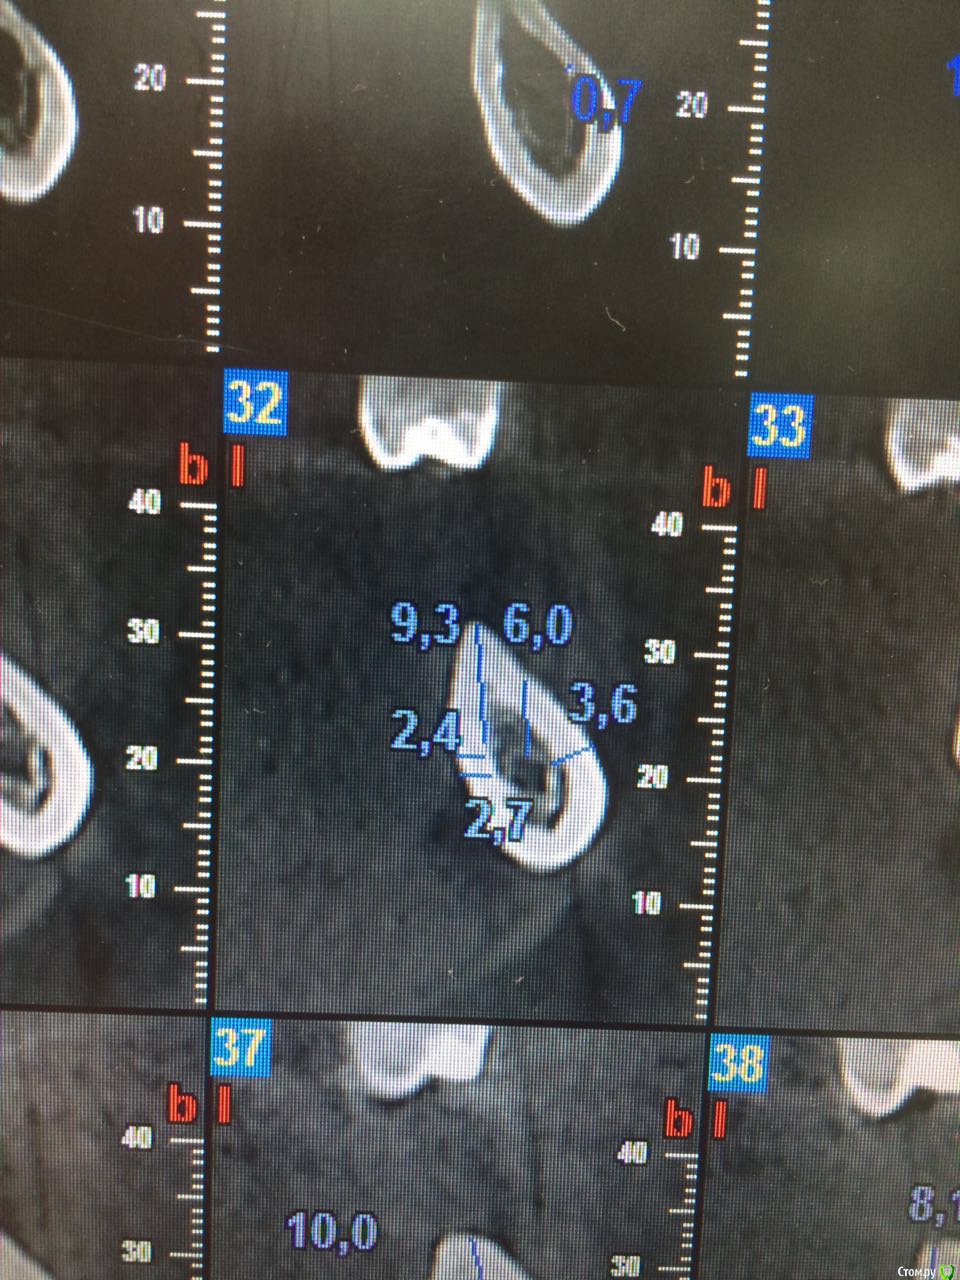

ILGAMSA Опубликовано 8 февраля, 2016 Автор Поделиться Опубликовано 8 февраля, 2016 Вот, кстати... одна из первых крыш. http://s019.radikal.ru/i635/1602/64/11cee0f97d29.png http://s017.radikal.ru/i414/1602/56/aecc99a5bada.png http://s017.radikal.ru/i410/1602/cf/78349eaaa0e5.png Через 4 месяца http://s020.radikal.ru/i717/1602/15/b062388ed059.png И еще через три http://s019.radikal.ru/i607/1602/69/fac3b85c606e.png и кт через 3.5 года http://s018.radikal.ru/i516/1602/cb/3c9299d6ba33.png http://s012.radikal.ru/i319/1602/e8/501e0be4e61a.png 2 Ссылка на комментарий

carloss Опубликовано 8 февраля, 2016 Поделиться Опубликовано 8 февраля, 2016 лучше бы что-нить прицельное, а ещё лучше в динамике.. Ну или кт, где дырка импланта по центру видна.. А то как говорил doka, я таких срезов могу нарезать)) Ссылка на комментарий

ILGAMSA Опубликовано 24 июня, 2016 Автор Поделиться Опубликовано 24 июня, 2016 лучше бы что-нить прицельное, а ещё лучше в динамике.. Ну или кт, где дырка импланта по центру видна.. А то как говорил doka, я таких срезов могу нарезать))http://s017.radikal.ru/i414/1606/bf/451a848dd77e.jpg Ссылка на комментарий